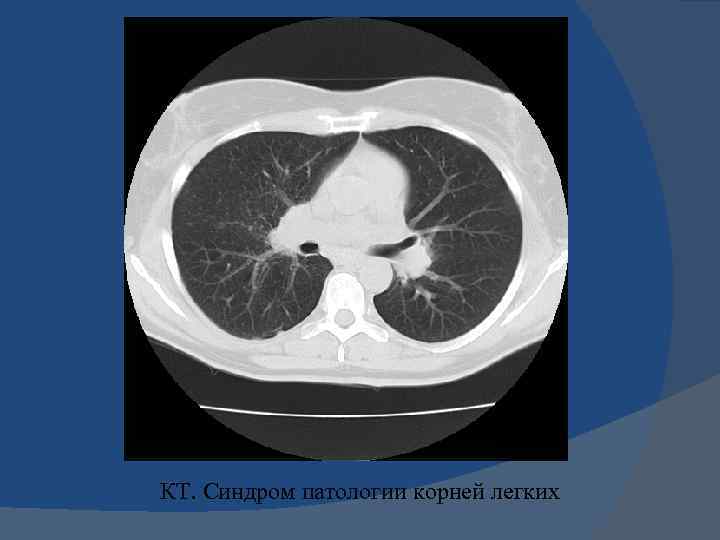

Синдром патологии корня легкого неструктурность и расширение корня легкого Причины патологии корня -увеличение лимфатических узлов – лимфаденопатия, -нарушение гемодинамики – -ЛВГ и ЛАГ

СИНДРОМ ПАТОЛОГИИ КОРНЯ ЛЕГКОГО НЕСТРУКТУРНОСТЬ И РАСШИРЕНИЕ КОРНЯ ЛЕГКОГО

Критерии структурности корня легкого 1. Ширина легочной артерии – до 15 мм; 2. Визуализация промежуточного бронха (10 мм); 3. Сужение к периферии легочной артерии; 4. Четкие, ровные контуры легочной артерии.

Критерии структурности корня легкого 1. Четкие, ровные контуры легочной артерии. 2. Ширина легочной артерии – до 15 мм; 3. Визуализация промежуточного бронха (10 мм); 4. Сужение к периферии легочной артерии;

Синдром патологии корня легкого неструктурность и расширение корня легкого Причины патологии корня -увеличение лимфатических узлов – лимфаденопатия, - нарушение гемодинамики – ЛВГ и ЛАГ

КТ. Синдром патологии корней легких